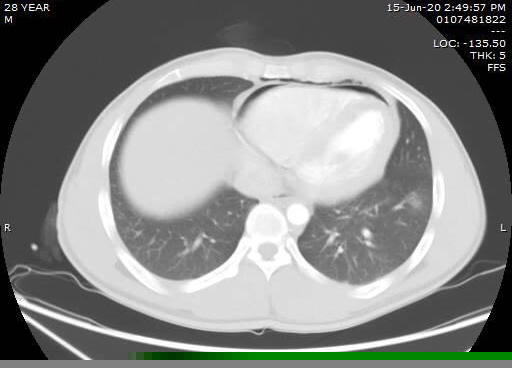

Hình ảnh chụp cắt lớp tràn khí và dịch khoang màng tim của bệnh nhân B.(ảnh BV.QN)

Ths.Bs Phạm việt Hùng – Trưởng khoa Ngoại, Bệnh viện Đa khoa tỉnh Quảng Ninh người trực tiếp phẫu thuật cho anh B cho biết : “Trường hợp của bệnh nhân B. bị ngã xuống vực sâu gần 30m với vết thương nặng ở ngực và gãy chân trái. Trong ranh giới giữa sự sống và cái chết, bệnh nhân đã vượt qua đau đớn, tự leo lên để nhờ sự trợ giúp của người đi đường thì thực sự đáng khâm phục. Khi tuyến dưới xin hội chẩn qua phim CT, chúng tôi nhận thấy cần được phẫu thuật xử trí gấp... May mắn là vết thương màng tim hở, máu thoát ra ngoài nên bệnh nhân không bị chèn ép tim, cơ tim không bị rách, nhờ vậy mà tăng thêm cơ hội sống khi tới viện ... Với nghị lực mạnh mẽ cùng sự phối hợp cấp cứu liên viện kịp thời mà bệnh nhân đa chấn thương kèm vết thương tim đã vượt qua cơn nguy kịch và phục hồi ổn định”.